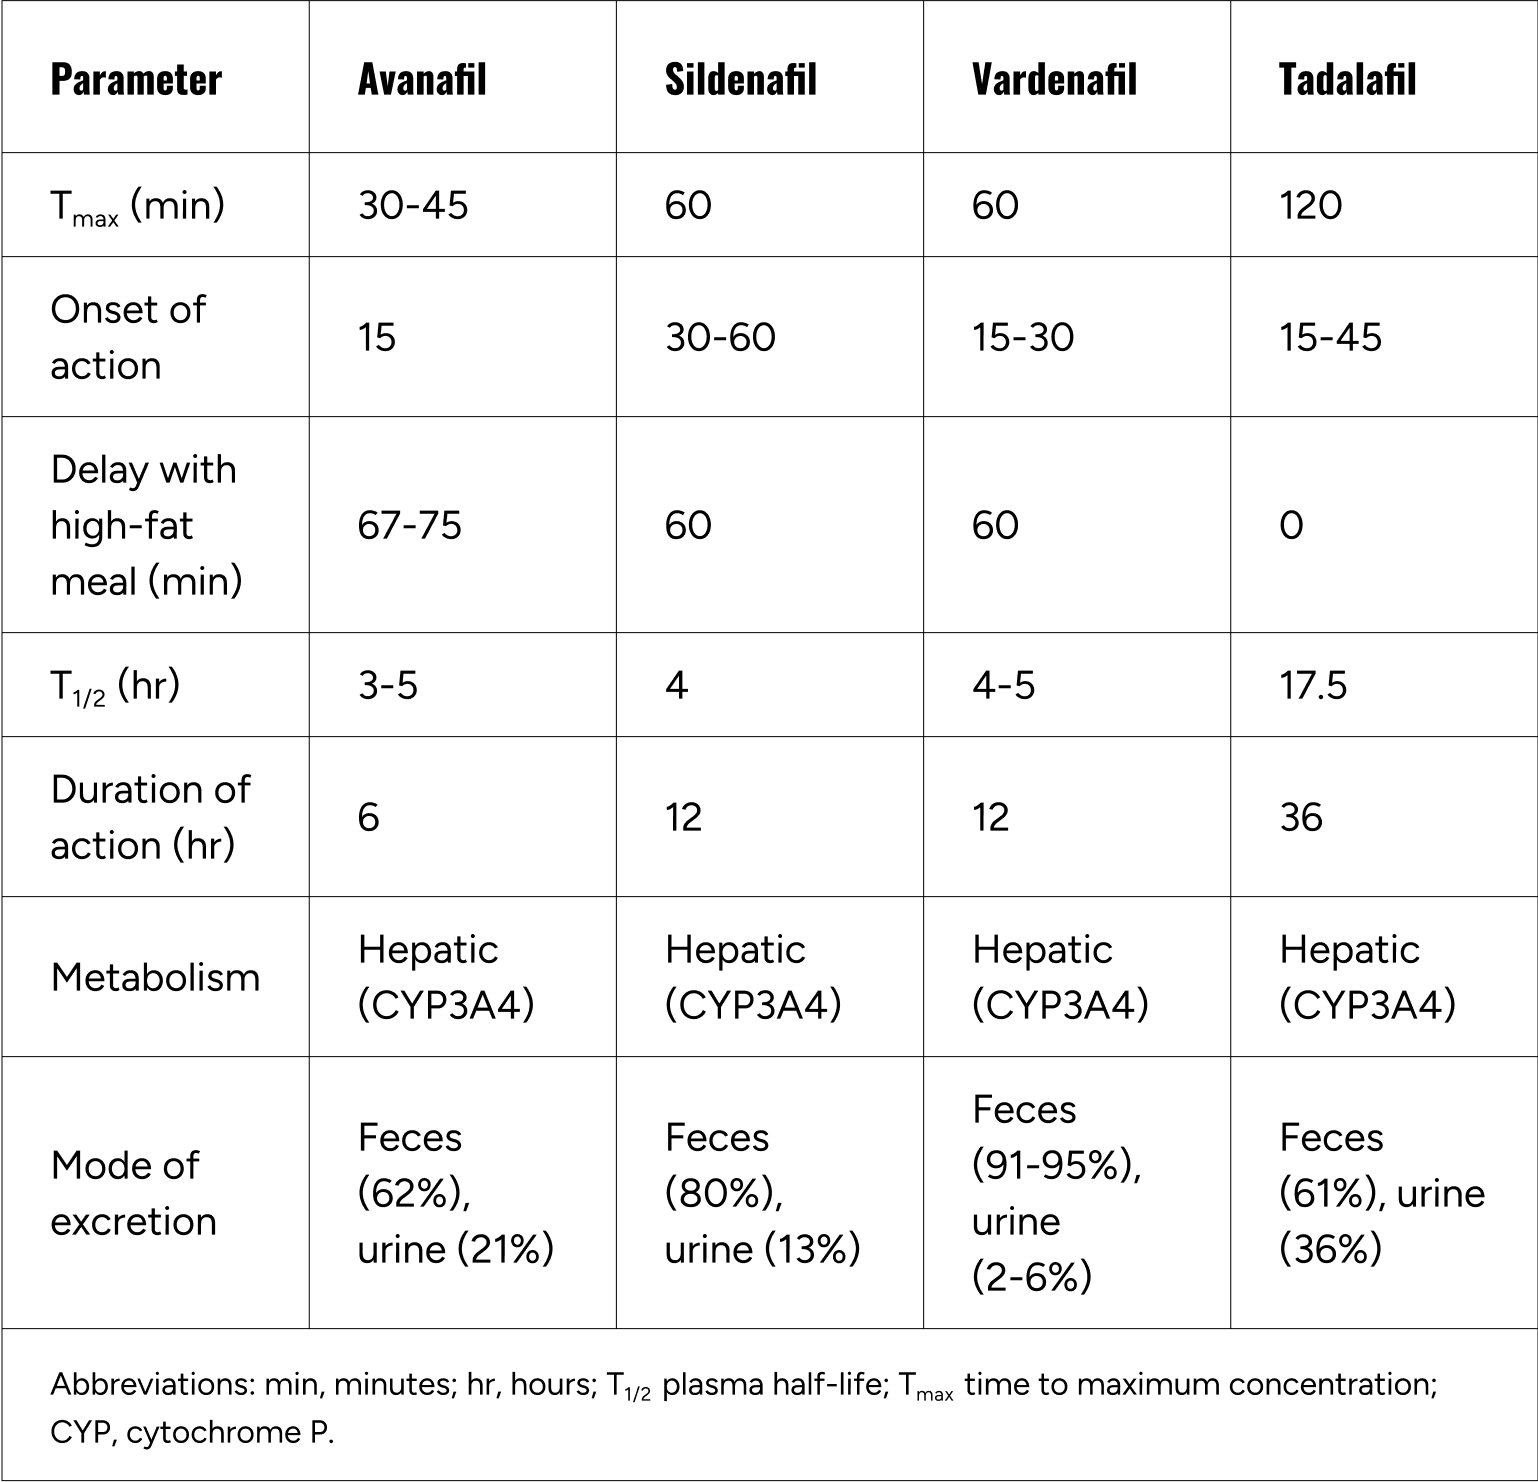

Tadalafil is the active ingredient in the erectile dysfunction drug Cialis. In the same way that it promotes blood flow to the penis, tadalafil improves blood flow to your brain and arouses emotions, thereby improving cognitive function and lowering the risk of chronic conditions like dementia from progressing. Like Viagra, tadalafil is a PDE5 inhibitor. It works by inhibiting an enzyme in the body called cyclic guanosine monophosphate-specific phosphodiesterase type 5, also known as PDE5. Through this process, tadalafil decreases intracellular calcium in smooth muscle, causing the muscle tissue to relax. This relaxation of muscles facilitates better blood flow. Tadalafil has a long half-life of around 17.5 hours, which means it sustains cognitive benefits throughout the day.

Vardenafil is the active ingredient in the drug Levitra. Considered the most potent PDE5 inhibitor, vardenafil promotes blood flow to the brain like tadalafil, but its shorter half life means you’ll notice the effects faster, in as little as 15 minutes. Because these vasodilating effects occur quickly, taking the medication before a demanding event results in sharper mental performance so you can deliver your best self.

Summary of pharmacokinetics of select PDE5 inhibitors

Fig.3 - Katz EG et al. Avanafil for erectile dysfunction in elderly and younger adults: Differential pharmacology and clinical utility. Ther Clin Risk Manag. 2014;10:701-11.